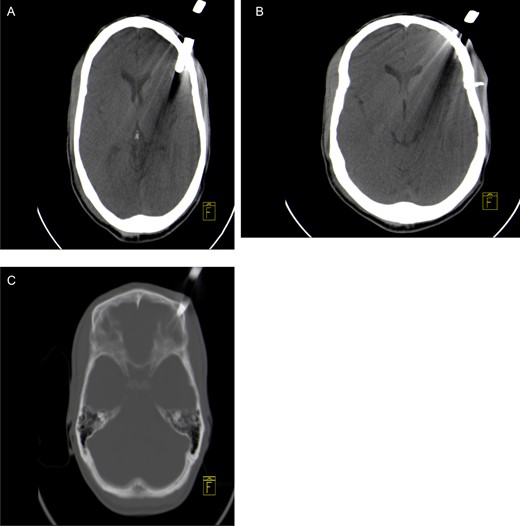

Axial non-contrast CT brain scan showing a garden fork prong in the left frontal parenchyma with associated artefact (A) and loose bone fragment in left frontal soft tissue (B). Axial CT bone window showing left frontal bone fracture caused by the fork (C).

A 30-year–old male patient was stabbed in the head with a garden fork following a dispute with a neighbour. He was initially assessed at his local hospital, which referred him to our neurosurgery unit for further management. On arrival, he was haemodynamically stable and was noted to have a retained garden fork in the left frontal area. His Glasgow Coma Scale (GCS) was 14/15, with no associated neurological deficits. He was noted to have left peri-orbital swelling, but vision was intact. There was no active bleeding from the wound and no other associated injuries. He was intoxicated at the time of examination and had a generalized tonic–clonic seizure in the emergency department, which was aborted. He was loaded with phenytoin and put on maintenance therapy. A computerized tomographic (CT) scan of the brain showed a retained garden fork in the frontal area (Fig. 1). The garden fork prong had penetrated the left frontal cortex; however, it caused a lot of artefact making visualization of parenchymal tissue damage difficult to appreciate (Fig. 2). Tetanus toxoid was administered and he was taken to the operating theatre for removal of the garden fork under general anaesthesia. At induction, intravenous first-generation cephalosporin and metronidazole were administered for prophylaxis.